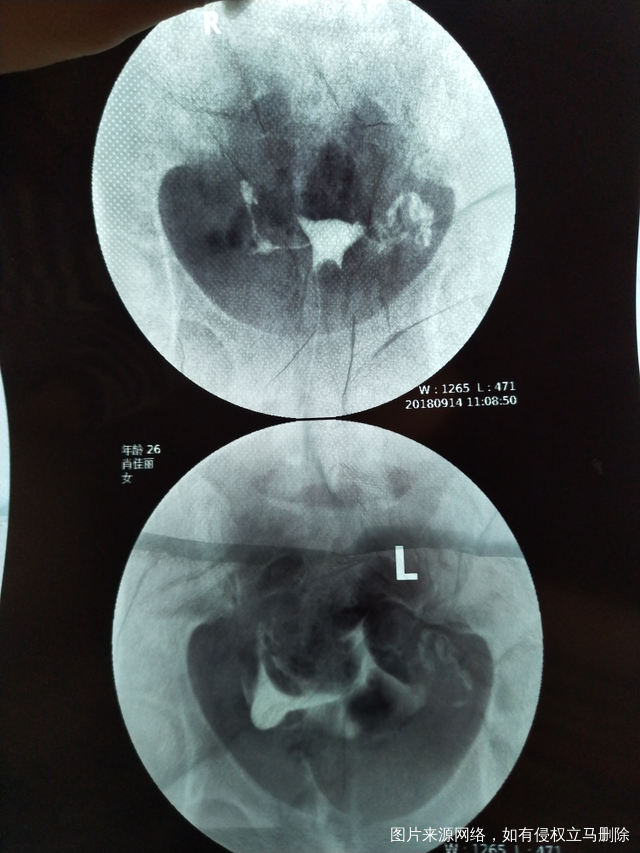

今天做了造影 医生帮我看下怎么样吧?